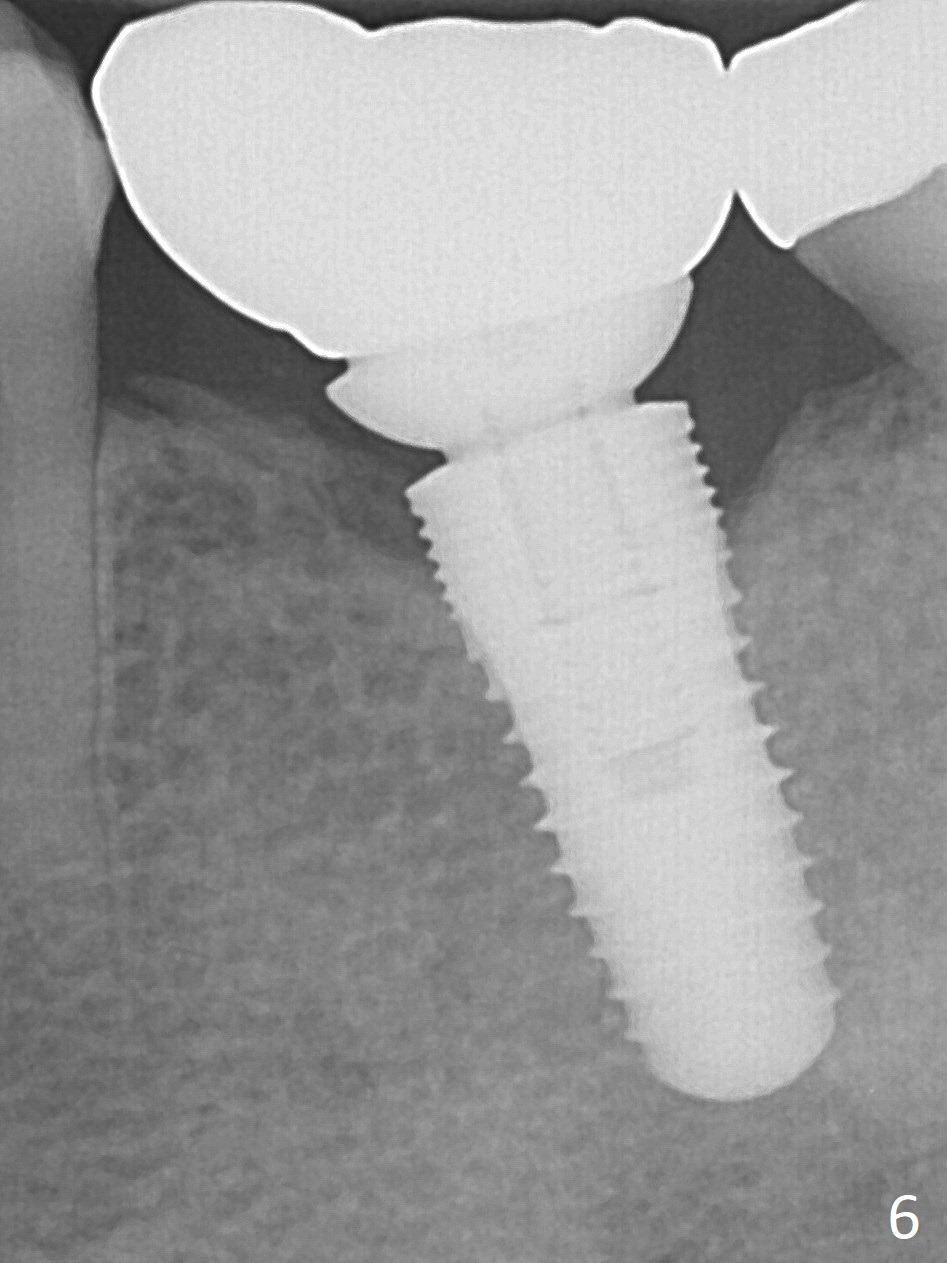

It appears that the diameter of the implant should be also controlled. A smaller implant may not lead to thread exposure and ultimately bone loss. It remains to be true 7 months post cementation (Fig.5). It appears that a 4.5 mm implant is better choice. There is no sign of periimplantitis. Oral hygiene, soft and hard tissues remains basically the same 2 years post cementation (Fig.6). The mesial open margin may be related to failure of impression material to get to the margin in spite of laser gingivectomy.